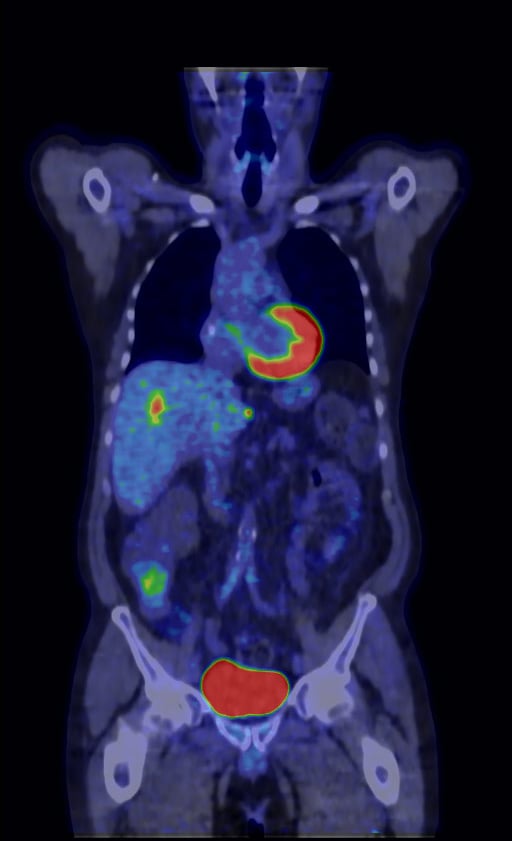

Over the last decade, positron emission tomography (PET) image reconstruction technology has been designed to provide better image quality, reduced acquisition time and lower injected dose. Current PET iterative reconstruction technologies, such as time of flight (TOF) and OSEM, force a compromise between image quality and quantitation. GE Healthcare said its Q.Clear technology brings convergence to PET imaging without the need for compromise between quantitation and image quality.

Clinicians not only want the ability to detect smaller lesions, but the ability to determine earlier whether the patient is responding to current treatment. Q.Clear aims to help in both areas by providing better quantitation accuracy for truly personalized medicine. Coupled with Q.Suite, which introduced the importance of eliminating variability such as respiratory motion, Q.Clear can enable clinicians to assess treatment response accurately.